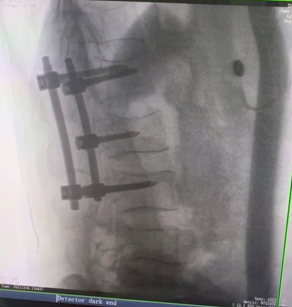

例如治療先天性脊柱側后凸畸形,由于脊柱自身復雜的解剖結構限制,使得脊柱外科手術對于準確度有著較高要求。以往我們只能采用傳統(tǒng)的正側位圖像來判斷螺釘置入的位置,現(xiàn)在三維C形臂特有的類CT斷層成像,使得治療過程可視化,立體化,在術中非常直觀地判斷螺釘植入的準確度??捎行б龑g者植入后路螺釘并切除半錐體。同時可以在術中實時驗證手術效果。有效地縮短了手術時間,降低手術風險,避免了不必要的術后翻修手術。